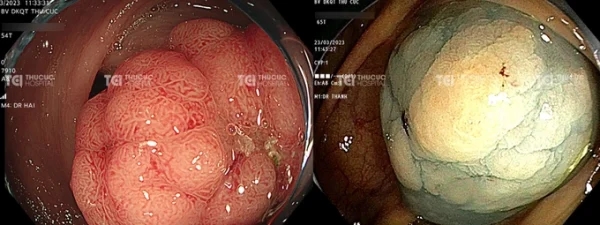

Hình ảnh khối polyp đại tràng kích thước lớn với bề mặt sung huyết, chia múi.

Khi phát hiện polyp, bác sĩ sẽ áp dụng các kỹ thuật công nghệ nội soi hiện đại nhằm hỗ trợ đánh giá tình trạng của polyp để đưa ra chỉ định cắt polyp qua nội soi. Thông thường, với những polyp kích thước từ 0,2-2cm là có thể cắt. Đặc biệt, với những polyp có ngoại hình bất thường như bề mặt sung huyết chia múi hoặc nhiều rãnh, có cấu trúc răng cưa,.. đều được đánh giá là có nguy cơ cao nên sẽ được can thiệp cắt bỏ ngay.